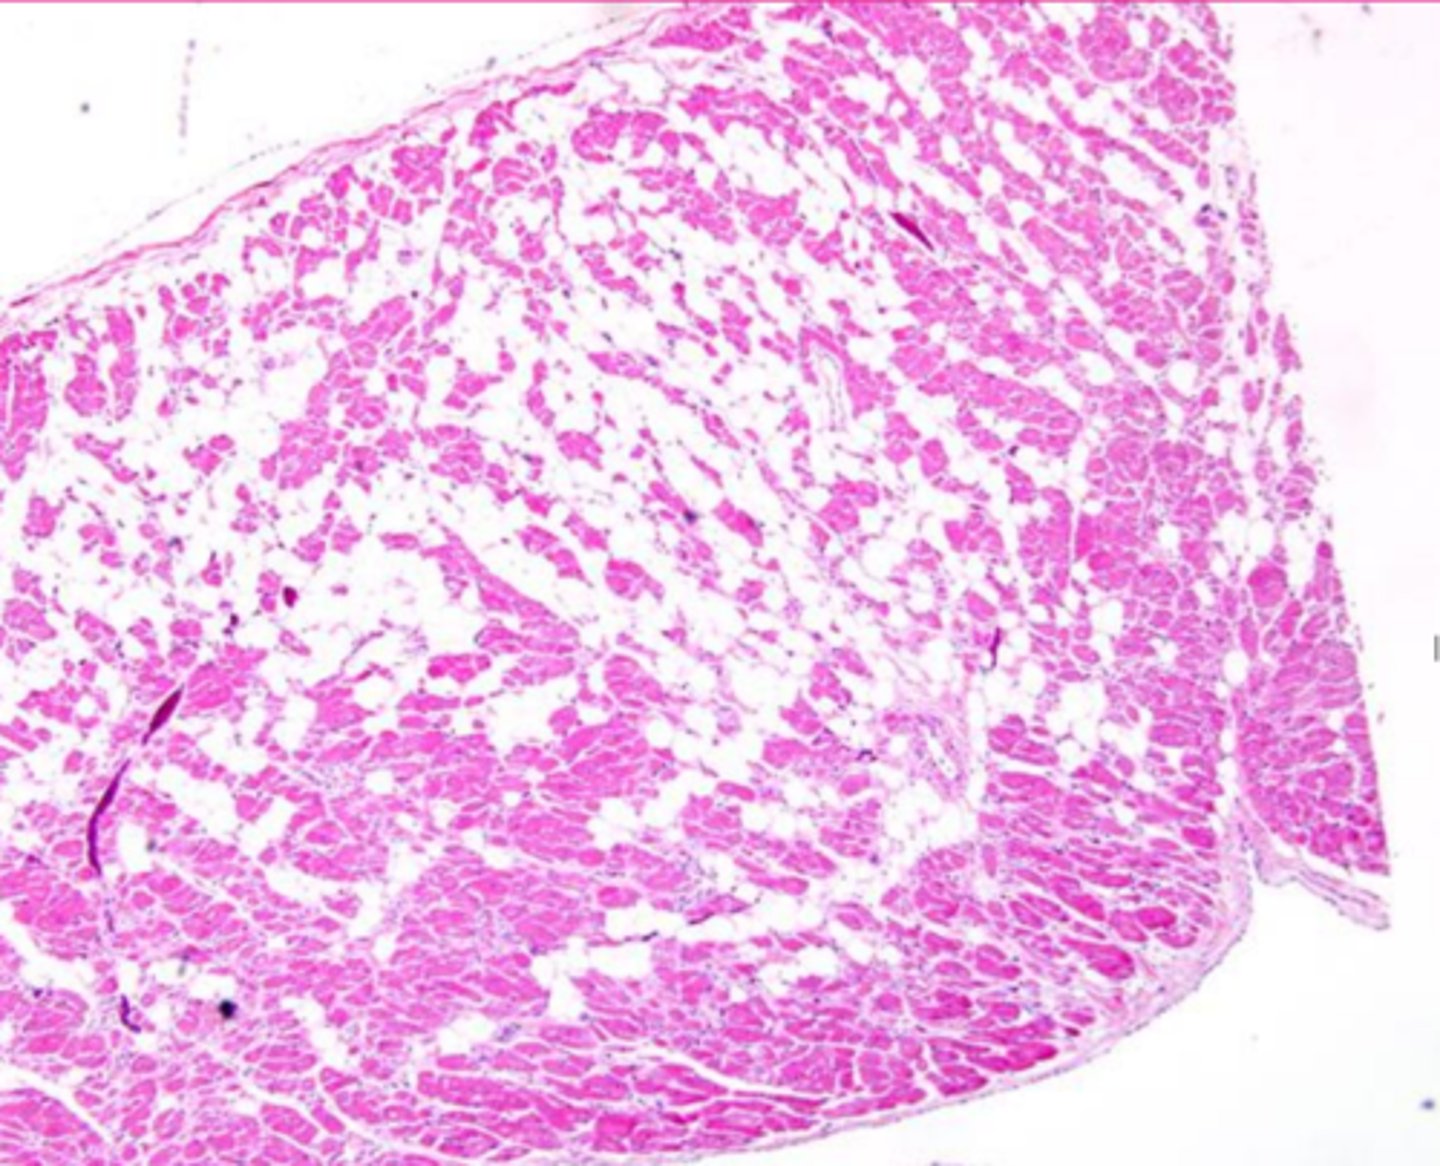

myocardial fibrosis

Describe this extracellular inclusion (heart muscle)

<p>Describe this extracellular inclusion (heart muscle)</p>

fatty infiltration

Describe the extracellular accumulation (this is a heart muscle)

<p>Describe the extracellular accumulation (this is a heart muscle)</p>